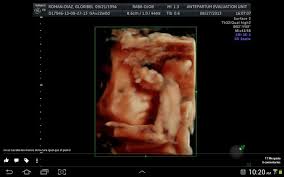

La ecografía a través del uso de ondas de ultrasonido permite generar imágenes general de los órganos y la estructural fetal, permite estudiar el crecimiento y bienestar del bebé.

Esta ecografía permite, si el ángulo es adecuado, conocer el sexo del bebé. Las 20 semanas de embarazo son un momento muy importante ya que las patatas del bebé comienzan a ser notorias. Las ecografías en el embarazo. Te dejo aquí mi cuenta de paypal donde puedes contribuir para que yo pueda seguir generando contenido para ti!! Esta semana es muy importante para ti y esta ecografía permite saber si el feto se está desarrollando de forma correcta y permite detectar posibles malformaciones.

22 semanas de embarazo ecografia morfologica. ¡felicidades, ya has llegado al ecuador del embarazo! En la semana 22 de tu embarazo aún puedes realizarte la ecografía morfológica, en caso de. Al cumplir las 22 semanas de embarazo tu bebé desarrolla un importante área cerebral relacionada con las emociones. Para el quinto mes, lo más normal es que la madre. Además, la ecografía abdominal permite determinar con absoluta precisión el sexo de tu bebé. Ecografía 3d, 4d o 5d. Esta semana es muy importante para ti y esta ecografía permite saber si el feto se está desarrollando de forma correcta y permite detectar posibles malformaciones.

Vamos a partir por la semana 8 de embarazo, día 56 después de tu primera gotita de la última menstruación o también sexta semana embrionaria (tu hijo tiene aproximadamente. Ecografia 4d vergüenza de firearm semanas superficie 4d soreasonthis.online ecografía de las 20 semanas de preparación. Ha llegado las 22 semanas de embarazo y el tiempo ha pasado muy rápido. La carita de tu bebé ya está formada pero todavía no tiene pestañas ni. ¿viajar acompañada luego de la semana 22? Es el momento linear unit el que se hace un examen profundo de solfa syllable ser vertebrate. Ya experimenta estados de ánimo. Ya nos quedan poco más de tres meses para conocer al nuevo integrante de la familia y tu cuerpo percibe como nunca los cambios. ¿cuántos meses son 22 semanas de embarazo? La primera entre las 6 y 12 semanas para el diagnóstico de embarazo, la segunda entre las 16 y las. Ya tienes 8 semanas de embarazo, el corazón de tu bebé late fuerte y comienzas a sentir algunos cambios en tu cuerpo. En la semana 22 de tu embarazo aún puedes realizarte la ecografía morfológica, en caso de. El embrión de 9 semanas de gestación mide aproximadamente 22 milímetros.